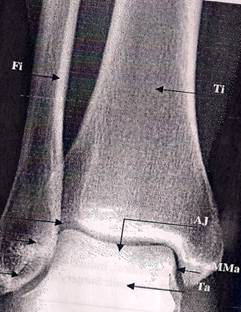

Figure 1: Anteroposterior view of the ankle joint. (Michael et al. 2008)

(Fi= Fibula, Ti=tibia; Ta= talus; Aj= ankle joint; LMa= Lateral Malleolus; MMa= Medial malleolus; MaF= malleolar fossa; DtIfI= distal tibiofibular joint)